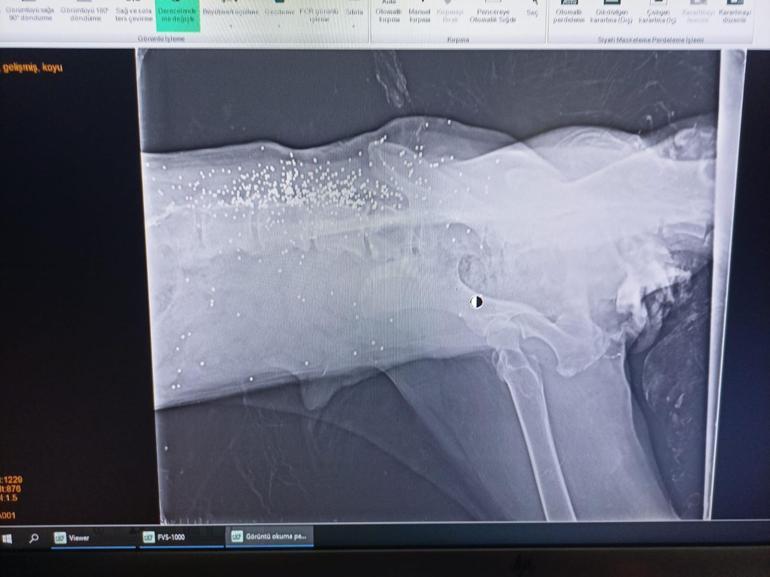

Olay, geçtiğimiz gün Doğancı köyünde gerçekleşti. Köy içerisinde ilerleyen bir sürücü, yolda yatan bir köpeğin üzerinden geçerek yoluna devam etti. Köpeğin acı içinde kıvrandığı anlar, çevredeki bir evin güvenlik kamerasına yansıdı. Veteriner hekimler, yaralı köpeğin arka bacaklarında çok sayıda kırık tespit etti. Yaralı köpek, Bolu Belediyesi Veteriner İşleri Müdürlüğü’ne ait hayvan hastanesinde tedavi altına alındı. Yapılan röntgen incelemesinde, köpeğin daha önce tüfekle vurulduğu ve vücudunda 300-400 saçma izi bulunduğu belirlendi.

Bolu Belediye Başkanı Tanju Özcan, hayvan hastanesini ziyaret ederek köpeğin sağlık durumu hakkında bilgi aldı. Köpeğin ezilmesi ve tüfekle vurulmasına tepki gösteren Başkan Özcan, “Hayvan hastanemize getirilen köpeğimize veteriner hekimlerimiz gerekli müdahaleleri yaptılar. Ancak bizim için sürpriz bir gelişme oldu. Biz sadece vahşi bir insanın bu hayvanı ezdiğini düşünüyorduk. Oysa çekilen röntgende şu ortaya çıktı: Bu hayvan daha önce saçmalarla vurulmuş” dedi.

Yapılan incelemede, köpeğin vücudunda 300-400 civarında saçma izi tespit edildiğini belirten Özcan, “Bu nasıl bir insanlık? Bu tür insanlar bu hayvandan ne ister? Anlamak mümkün değil. Ama sağ olsun arkadaşlarımız ellerinden geleni yapıyorlar. Şu an hayati tehlikesi yok. İnşallah arka bacakları da yürüyecek düzeye gelir. Bu konuyla ilgili hukuki bir süreç başlatıldı. Valilik gerekli tespitleri yaptı. Belediye Meclisi olarak hayvanlara kötü muamele yapanlar hakkında ağır para cezaları öngörüyoruz. Bu cezaları tatbik edeceğiz. Hayvanlarımıza bu tür muamele yapanları insanlık adına affetmeyeceğiz” ifadelerini kullandı.